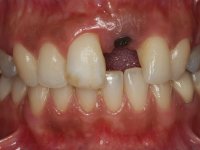

3) Colocação de um implante no espaço criado na zona do 21 associada a uma regeneração óssea guiada da zona,

4) Reabilitar prostodonticamente o implante com um coto de oxido de zirconio e uma coroa de cerâmica vítrea prensada de dissilicato de lítio no sentido de obter o resultado estético pretendido.

A confecção de um coto de óxido de zircónio com uma coroa de cerâmica vítrea prensada de dissilicato de lítio mimetizou perfeitamente os dentes vizinhos.